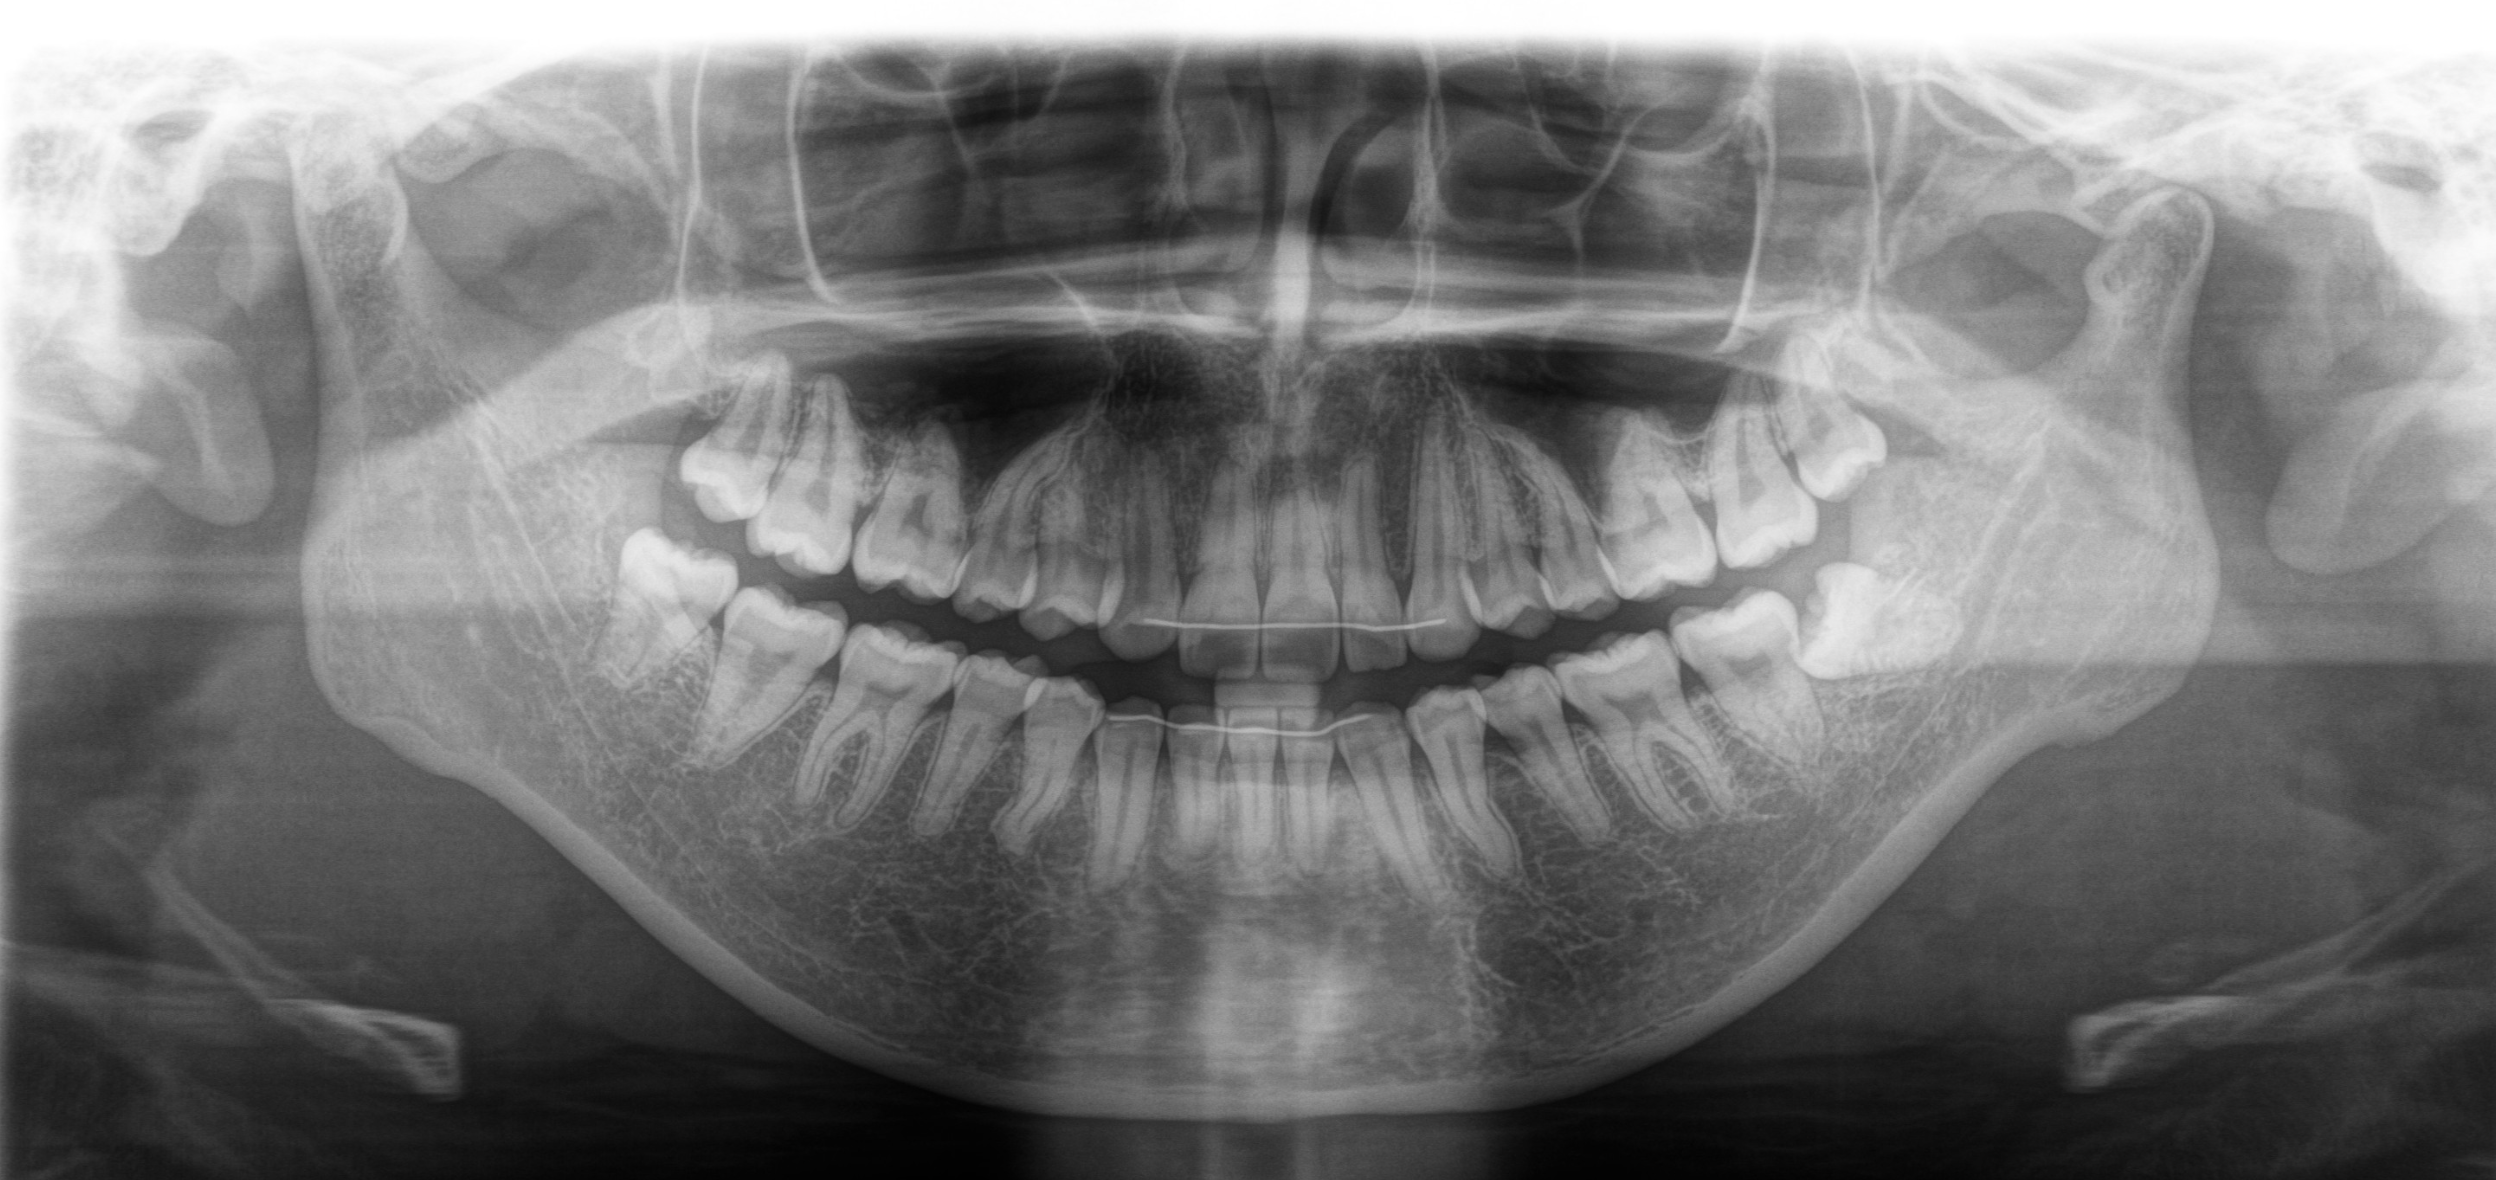

口の中を確認し、レントゲンや必要に応じてCTで、親知らずの位置や神経との関係をチェックします。

神経や上顎洞に近いケースでも、画像診断を踏まえて安全に配慮した抜歯

難症例(水平埋伏・骨の深い埋伏など)にも対応可能

完全に横向きに埋まっている水平埋伏智歯

これらすべてを、岸先生が確かな判断と手技で対応します。